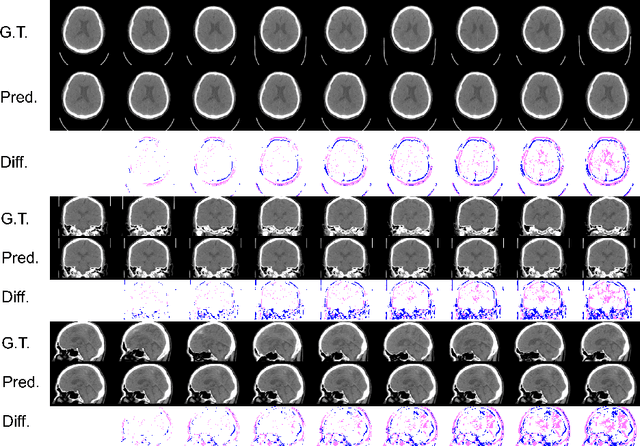

Abstract:From birth to death, we all experience surprisingly ubiquitous changes over time due to aging. If we can predict aging in the digital domain, that is, the digital twin of the human body, we would be able to detect lesions in their very early stages, thereby enhancing the quality of life and extending the life span. We observed that none of the previously developed digital twins of the adult human body explicitly trained longitudinal conversion rules between volumetric medical images with deep generative models, potentially resulting in poor prediction performance of, for example, ventricular volumes. Here, we establish a new digital twin of an adult human body that adopts longitudinally acquired head computed tomography (CT) images for training, enabling prediction of future volumetric head CT images from a single present volumetric head CT image. We, for the first time, adopt one of the three-dimensional flow-based deep generative models to realize this sequential three-dimensional digital twin. We show that our digital twin outperforms the latest methods of prediction of ventricular volumes in relatively short terms.